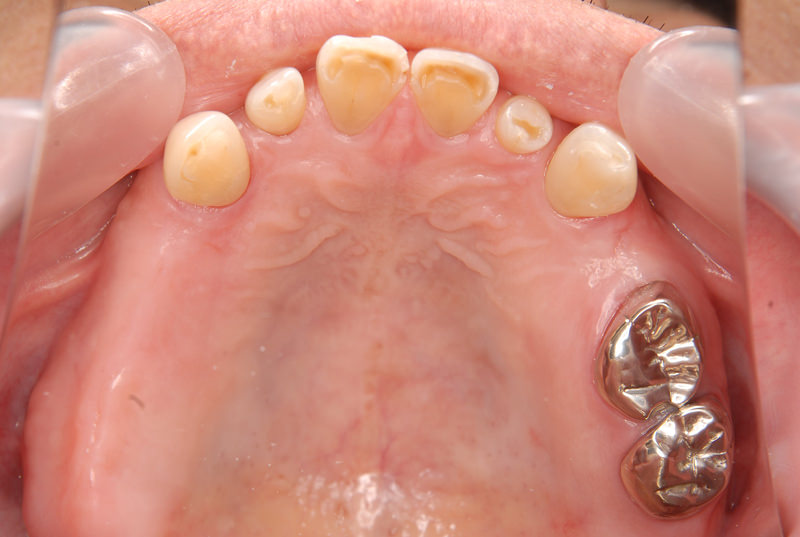

症例2【70代女性】主訴 義歯がわずらわしい・しっかり噛みたい

治療前

治療後(2年経過)

主訴 上顎のみ部分義歯を使用しているが、入れ歯が煩わしい、固定制のインプラントにして欲しいと来院。

左右上顎第一大臼歯相当は、骨の高さが不足しており、ソケットリフト(骨造成)の必要があり、左右第一小臼歯、第一大臼歯支台のインプラントブリッジを提案。

採血で得られた、CGFメンブレンとAFGブロック(人工骨β‐TCPとAFGを混ぜたブロック)を使用し骨を挙上し、インプラントを埋入。

右下のブリッジも、短根歯で動揺が激しい為に抜歯し、インプラント埋入。

上顎の免荷期間は約4ヶ月、下顎の免荷期間は約2ヶ月を経て、仮歯を装着、リハビリをし、メタルボンド(金属焼付ポーセレン)を装着。

費用 280万(オペ・ソケットリフト・人工骨・採血による濃縮血小板生成・仮歯・最終補綴物まで含む)